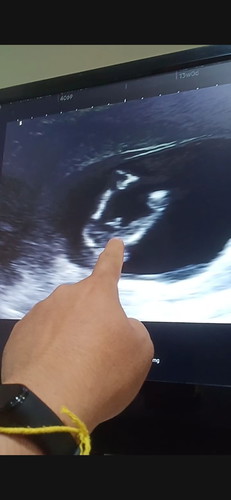

วันนี้คุณหมอซาวน์เพศน้องให้ค่ะ อย่างที่เห็นตามภาพค่ะ แต่คุณหมอยังไม่คอนเฟิร์ม ขอความคิดเห็นคุณแม่ท่านอื่นๆหน่อยค่ะ 13 w 2 d ค่ะ